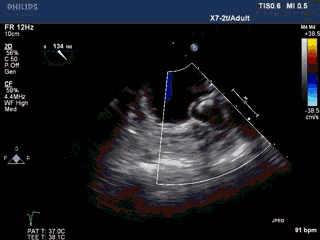

术前准备——TEE评价左心耳结构

左心耳呈多分叶状,口部梳状肌发达。